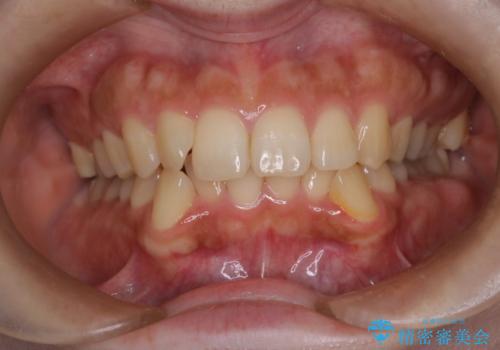

ディープバイト改善のためのインビザライン治療

- 治療計画

ディープバイトの治療には、奥歯の高さや前歯の位置に対する繊細な調整が必要です。本症例では、インビザラインによる歯列拡大を行うことで、噛み合わせを改善し、歯並び全体を整えました。治療過程では、歯間のスペースを確保するため、IPR(インタープロキシマルリダクション)を適宜行い、無理なく歯列の調整を行いました。治療後は、歯並びが大きく改善され、患者様の見た目にも大きな変化が現れました。インビザラインは透明で目立たず、治療中の見た目を気にされる患者様にも配慮した治療法です。